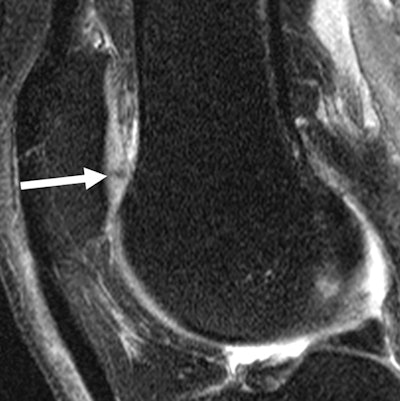

MR images of the right knee show signal abnormalities at baseline and subsequent defects at the 48-month follow-up. Above image shows a hyperintense signal abnormality in the patella at baseline (arrow). Image below shows the development of a fissure in the same patient (arrow) at 48 months. Images courtesy of Radiology.In an analysis by compartment, data revealed that cartilage signal abnormalities were most frequent in the patella (44 cases, 35%), followed by the lateral tibia (33 cases, 26%), trochlea (31 cases, 25%), medial femur condyle (10 cases, 8%), lateral femur condyle (7 cases, 6%), and medial tibia (1 case, 1%).